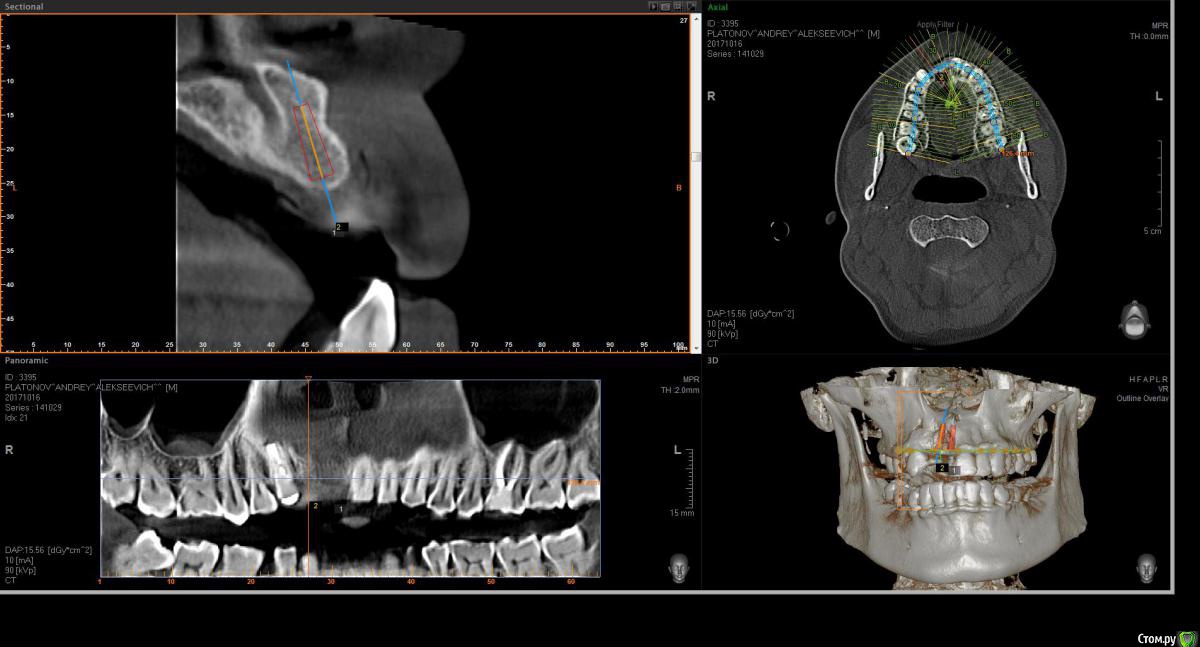

Eddie Опубликовано 23 октября, 2017 Поделиться Опубликовано 23 октября, 2017 (изменено) Здравствуйте! Подскажите по планированию имплантации. 11- удален 4-5 месяцев назад, 12-несколько лет назад. Пациент на данный момент носит съемник.как лучше позиционировать имплантаты? возможно ли обойтись без нкр, а поработать конденсорами? Еще смущает, что в области 11 возможно дефицит кости после удаления? Если ставить 11 чуть ближе к 21, то там условия по-лучше, но до 21 расстояние 1.5 мм или даже чуть меньше!В клинике только Ankylos. Реально ли будет отпротезировать при таких позициях?Буду благодарен любым советам. P.S. пациент финансово не потянет нкр Изменено 23 октября, 2017 пользователем Eddie Ссылка на комментарий

Bier Опубликовано 25 октября, 2017 Поделиться Опубликовано 25 октября, 2017 не вижу уровня гребня. Фотки бы. По тому что я вижу, имплантат в область 12 с Анкилос как раз подойдет. + десна в область 12 и 11.Если это ваш первый кейс, боюсь, что вы его запорите. Ссылка на комментарий

Eddie Опубликовано 25 октября, 2017 Автор Поделиться Опубликовано 25 октября, 2017 (изменено) не вижу уровня гребня. Фотки бы. По тому что я вижу, имплантат в область 12 с Анкилос как раз подойдет. + десна в область 12 и 11.Если это ваш первый кейс, боюсь, что вы его запорите.Спасибо за ответ. В клинике я один хирург! Отказаться вряд ли получится. Есть опыт установки имплантатов в области жевательных зубов, опыт работы с десной. Если всё-таки буду ставить, в области 12 в плане вестибуло-орального положения и наклона как лучше спозиционировать? Изменено 25 октября, 2017 пользователем Eddie Ссылка на комментарий

Bier Опубликовано 25 октября, 2017 Поделиться Опубликовано 25 октября, 2017 Нет, пациент готов еще без зуба походитьнаклон не имеет принципиального значения. Я бы ставил четко по гребню. Вестибуло-орально центр имплантата должен смотреть в слепую ямку предполагаемого зуба. Для этого начинать сверление нужно на 0,5-1мм нёбнее с давлением на нёбную стенку, чтобы имплантат в итоге не встал вестибулярно. Я бы откинул лоскут в области 12 и туннелировал офтальмологическим скальпелем область 11. Понадобятся внутрибороздковые разрезы в области 21з взять ССТ и завести его правую часть под слизистую в области 11з, а левую надеть на формик. Формирование овоида не ранее, чем через 6 недель после операции. Ссылка на комментарий